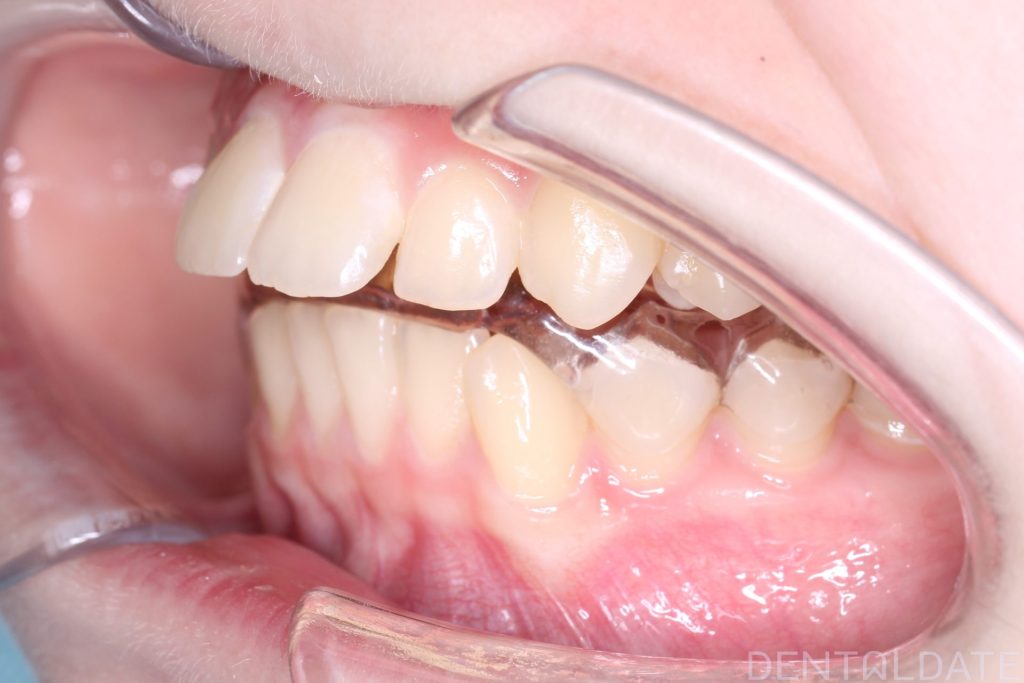

A splint was made in the therapeutic (correct) jaw position, ensuring there was no risk to the joint.

After a follow-up MRI confirmed the correct jaw position, braces were installed.